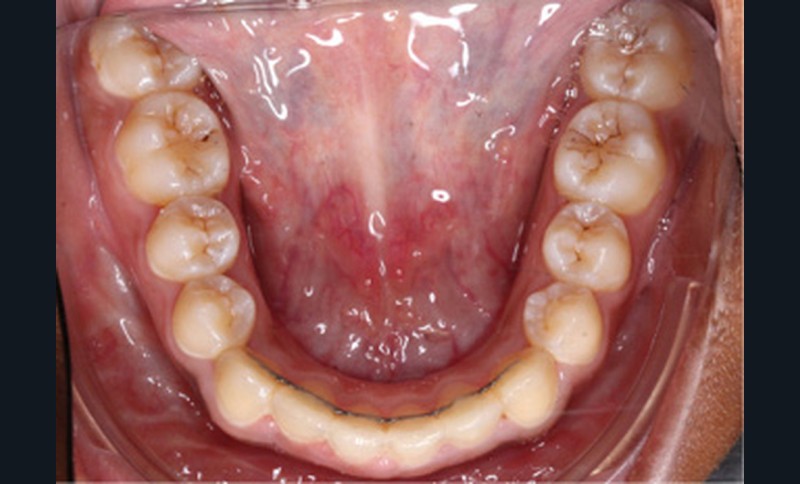

L’examen clinique endo-buccal révèle une denture adulte jeune avec un inversé d’articulé antérieur de 13 à 23, des tatouages gingivaux ethniques et des taches de décalcifications, un parodonte sain mais un brossage insuffisant.

L’arcade maxillaire est en V et la voûte palatine profonde. L’arcade mandibulaire a une forme en U (non-concordance des formes d’arcade) et présente des malpositions des dents cuspidées. La médiane mandibulaire est décalée à gauche de 2 mm ; le recouvrement antérieur est de 2 mm ; les molaires sont en classe III avec un surplomb inversé.